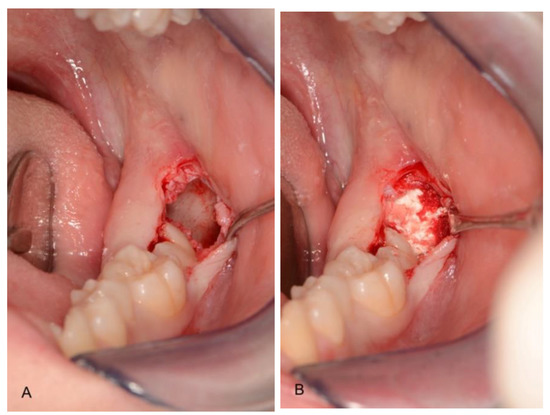

2.3. Surgical Technique

| Pre-filled syringe of polymer-coated granules together with a separate ampoule of polymer activator. This activator softens the polymer coating, creating a sticky surface. Granules are made of microporous calcium phosphates with pore sizes of 1 to 10 μm. | Hemostatic sponge with collagen of bovine origin, sterilized by beta radiations. |